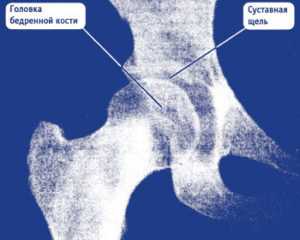

Снимок 1. На этом рентгеновском снимке изображен здоровый тазобедренный сустав. Мы можем здесь увидеть:

- правильную округлую форму головки бедренной кости;

- нормальных размеров суставную щель, т. е. достаточное расстояние между головкой бедренной кости и сочленяющейся с ней вертлужной впадиной.

Здоровый тазобедренный сустав. Фотография из архива доктора Евдокименко